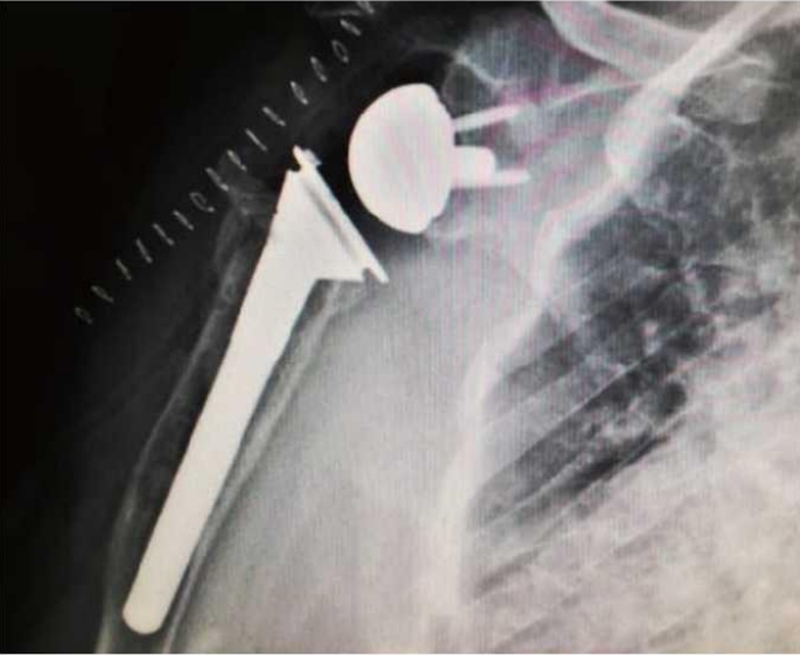

术后肩关节前后位X线片示右肩关节假体位置良好(图22)。

图22 术后肩关节X线片示右肩关节假体位置良好

肱骨近端骨折内固定术后并发症可导致肩关节功能严重受限,影响患者的日常生活。并发症中肱骨头畸形愈合与缺血性坏死发生率较高。翻修处理以假体置换为重要手段,这也是近年来肱骨近端假体临床应用快速发展的原因之一。